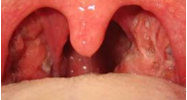

Es una infección de las amígdalas faríngeas por una bacteria.

Algunas bacterias, especialmente los estreptococos, suelen invadir estas amígdalas reproduciéndose en su interior, causando hinchazón y dolor, especialmente al tragar, acompañado de pus y material caseoso y un aroma fétido.

Las amígdalas faríngeas son dos masas de tejido linfático situadas en el interior de la boca, una a cada lado.

- Amígdalas rojas e hinchadas

- Una capa blanca o amarilla sobre las amígdalas